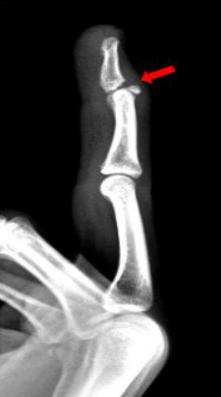

3、患者拇指被车床挤压,拍片如下:

右手拇指近节远端见斜行骨折透亮线,断端稍分离移位,右手拇指近节远端骨折。